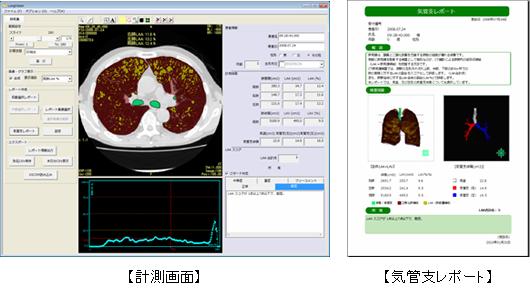

呼吸器外科疾患について | 藤田医科大学岡崎医療センター 呼吸器外科, CT肺気腫ソフトウェア「LungVision」新バージョンVer.2.1販売開始のお知らせ | サイバネットシステム株式会社のプレスリリース

CT肺気腫ソフトウェア「LungVision」新バージョンVer.2.1販売開始のお知らせ | サイバネットシステム株式会社のプレスリリース